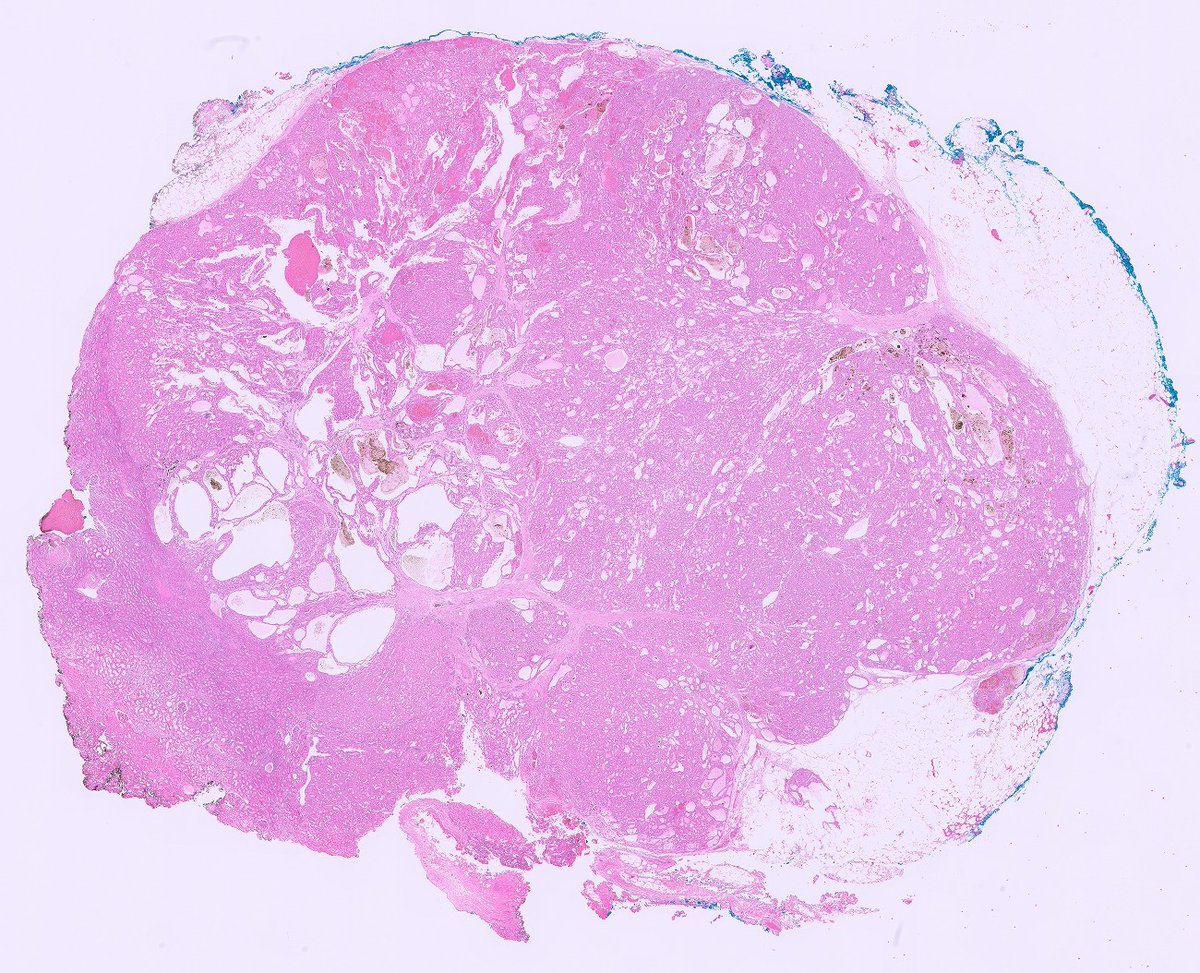

#GUpath nephrectomy chromophobe RCC 🔬features of so-called "pigmented microcytic" pattern chromoRCC and/or "eosinophilic" pattern chromoRCC